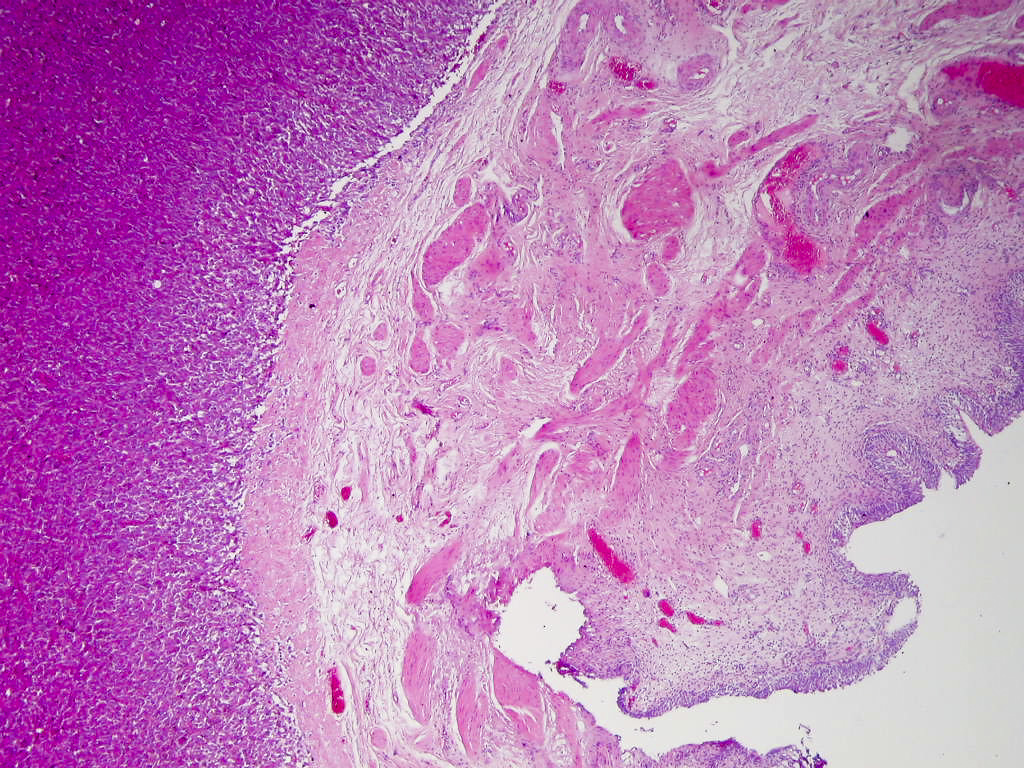

- Classic histologic morphology: monomorphic cells with abundant eosinophilic / amphophilic cytoplasm arranged in a nested / zellballen pattern and separated by fibrovascular septa with sustentacular cells

Gross description

- Genitourinary paragangliomas are typically tan-pink to violaceous, encapsulated and firm (Abdom Radiol (NY) 2022;47:1414, Abdom Radiol (NY) 2022;47:4032, BMC Urol 2023;23:21)

- Bladder paragangliomas are often submucosal or intramural and less frequently subserosal, with size at diagnosis up to 9.1 cm (mean: 3.9 cm)

- Small bladder paragangliomas: typically well circumscribed, round ovoid and homogeneous

- Larger bladder paragangliomas: usually more complex appearance with lobulation, peri and intratumoral vascularization and cystic / necrotic / hemorrhagic areas

- Bladder paragangliomas may have calcification (up to 20% of cases) or local invasion of the pelvic side wall, uterus, vagina and ovaries

Microscopic (histologic) description

- Typical morphology: epithelioid cells with abundant, eosinophilic / amphophilic, granular cytoplasm and round / ovoid, vesicular / salt and pepper nuclei, arranged in a nested / zellballen pattern and separated by fibrovascular septae with sustentacular cells (Am J Surg Pathol 2004;28:94, World J Clin Cases 2014;2:591, Endocr Pathol 2022;33:90)

Microscopic (histologic) images

Contributed by Theodorus H. van der Kwast, M.D., Ph.D., Michelle R. Downes, M.D., Debra L. Zynger, M.D. and David Cohen, M.B.B.Ch., M.D.